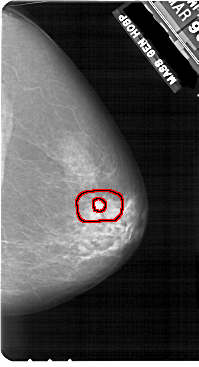

A_1908_1.LEFT_MLO

LEFT_MLO LINES 5491 PIXELS_PER_LINE 3511 BITS_PER_PIXEL 12 RESOLUTION 43.5 NON_OVERLAY

RIGHT_MLO LINES 5491 PIXELS_PER_LINE 3286 BITS_PER_PIXEL 12 RESOLUTION 43.5 OVERLAY

FILE: A_1908_1.RIGHT_MLO.OVERLAY

TOTAL_ABNORMALITIES 1

ABNORMALITY 1

LESION_TYPE MASS SHAPE IRREGULAR MARGINS SPICULATED

ASSESSMENT 5

SUBTLETY 4

PATHOLOGY MALIGNANT

TOTAL_OUTLINES 2

BOUNDARY

CORE